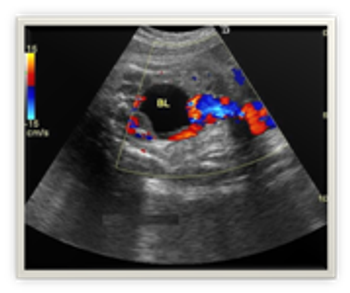

A routine ultrasound exam of a 28-week fetus revealed what looked to be a cystic lesion. The addition of Doppler, however, changed the diagnostic picture.